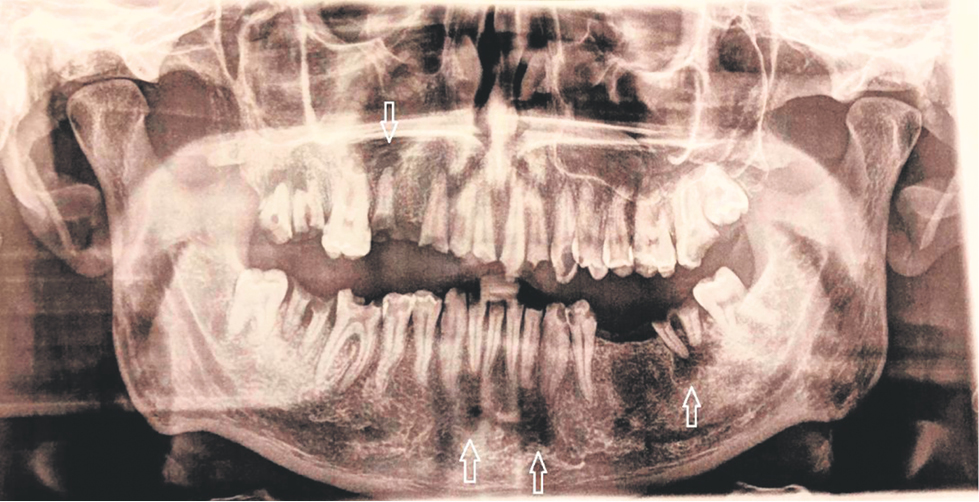

The patient was examined in a hospital (from September 27, 2018 to October 11, 2018) and the diagnosis of community-acquired left-sided lower-lobe pneumonia was established based on lung X-ray data. Lung Multispiral CT was not performed. Blood tests showed leukocytosis, left shift, 10-fold increase in CRP, Staphylococcus Haemolyticus was found in blood cultures. According to transthoracic Echo-KG, no pathology was revealed. The patient underwent a 12-day course of ceftriaxone and leflobact with positive dynamics of clinical, instrumental and laboratory data: during the week before discharge, there was no fever, pneumatization of the lungs according to the control radiographs recovered completely, the level of leukocytes and CRP returned to normal. Control blood cultures were not performed. However, just one week after discharge, the patient was re-hospitalized due to recurrence of fever. Again, leukocytosis and left shift were observed, procalcitonin exceeded normal values by 150 times. This time Staphylococcus Aureus was found in blood cultures (October 19, 2018). On the fourth day of hospitalization with echocardiography, vegetation was first detected on one of the pacemaker electrodes. Based on the data obtained, acute IE associated with the implanted pacemaker was diagnosed. The total duration of antibiotic therapy was 25 days. Unfortunately, there was no detailed information on the antibiotics used in the discharge reports. In order to find out the primary source of infection, the patient was examined by a dentist. An orthopantomogram (OPTG) revealed multiple granulomas of the upper and lower jaws. There were signs of periodontitis on teeth 15, 13, 12, 11, 21, 22, 23, 26, 27, 37, 45, 46; signs of chronic pulpitis 24, 25, 38, 35, 34, 33, 43, 44 (Fig. 1). It turned out that the patient himself did not attach much importance to the state of the oral cavity and had not visited the dentist in recent years. Considering the large extent of the lesion, a phased debridement of the oral cavity was started. By the time of discharge (November 13, 2018), there were no symptoms, the CBT and procalcitonin values returned to normal. The control culture showed the absence of microflora growth, with the control TTE there were no reliable vegetations in the area of the electrodes. Indications for surgical treatment of IE have not been formulated.

Fig. 1. Orthopantomogram of patient A. Arrows indicate multiple granulomas of the roots of the teeth of the upper and lower jaws.